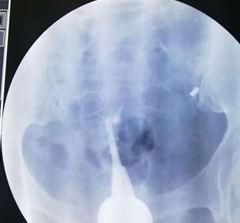

这是2年前的一个病例。一位广州市荔湾区桥中街村民邓XX,43岁,20年前第一胎生儿子后结扎。开放二胎后做输卵管吻合术,术中腹腔镜通液显示输卵管不通。术后第3个月找我做造影。我第一次做造影时造影导管插入宫颈浅进入不了宫腔,球囊固定不了造影管。我就用探针探测看看,探针只能进去宫腔3.5厘米,就在宫颈外口注造影剂,显示宫腔呈一长条状,形态同一段探针相仿,见图像1。我虽然是放射介入科医生,但是我是妇科生殖专业博士,在读妇科博士前,还专门进修妇科6个月,做过宫腹腔镜手术,插造影管对我来说是很简单的手术,基本上没有插不上造影管。做不了造影。但是,为诊断清楚,就没收费用,预约第二天请广州市红会医院原妇科主任,著名妇科腔镜专家陈燕辉主任出诊时,请陈主任插管再做一次造影。第二天,陈主任插造影管后,也固定不了造影管,就用探针探测宫腔,考虑重度宫腔粘连,宫腔近封闭,就用探针分离一下宫腔。我又在宫颈外口注入造影剂进行造影,显示宫腔近呈单叶片状,形似单角子宫,见图像2。然后追问病史,患者才讲10年前子宫大出血,做一次刮宫后再也没有月经。第二个月陈主任门诊行宫腔镜探查术证实重度宫腔粘连。重度宫腔粘连输卵管开口封闭,不管是做试管还是自然怀孕都不行,需要处理宫腔粘连才行。由于患者年纪大,和家属商量后就放弃再怀孕。因此,就没有处理宫腔粘连。符合宫腔粘连对于没有生育要求和没有痛经等不适者可以不手术的治疗原则。

结扎图1.png

图一